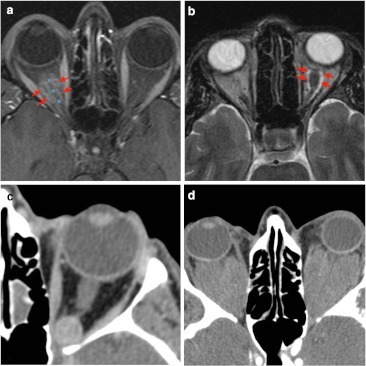

영상 소견

- CT: 잘 경계된 둥근 종괴, 균일한 조영증강

- MRI: T1 iso/low, T2 high, progressive/delayed enhancement (점진적 조영증강)